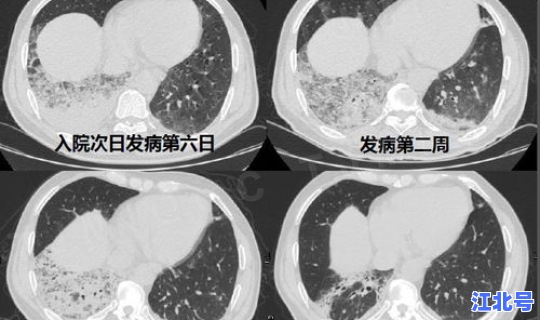

患者主要临床表现为发热 、乏力 ,呼吸道症状以干咳为主,并逐渐出现呼吸困难,严重者表现为急性呼吸窘迫综合征、脓毒症休克、难以纠正的代谢性酸中毒和出凝血功能障碍。部分患者起病症状轻微 ,可无发热 。